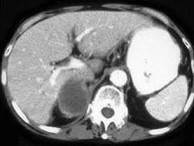

问题 男,75岁,右侧胸痛伴咯血3月余,胸部CT提示右侧中央型肺癌,请结合图像,作出诊断()

选项 A.右侧肾上腺囊肿 B.右侧肾上腺转移瘤 C.右侧肾上腺腺瘤 D.右侧肾上腺癌 E.右侧肾上腺嗜铬细胞瘤

答案 B